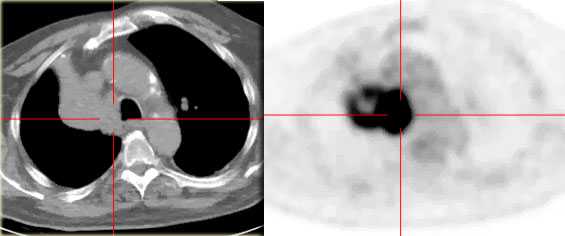

Ателектаз верхней доли правого легкого.

Оцените ниже лежащие изображения, а после продолжите чтение.

- Трехгранное затенение.

- Подъем правого корня легкого

- Облитерация загрудинного пространства (указано стрелкой).

На ПЭТ/КТ визуализируется опухоль легкого с обструкцией правого верхнедолевого бронха, как следствие ателектаз верхний доли правого легкого.